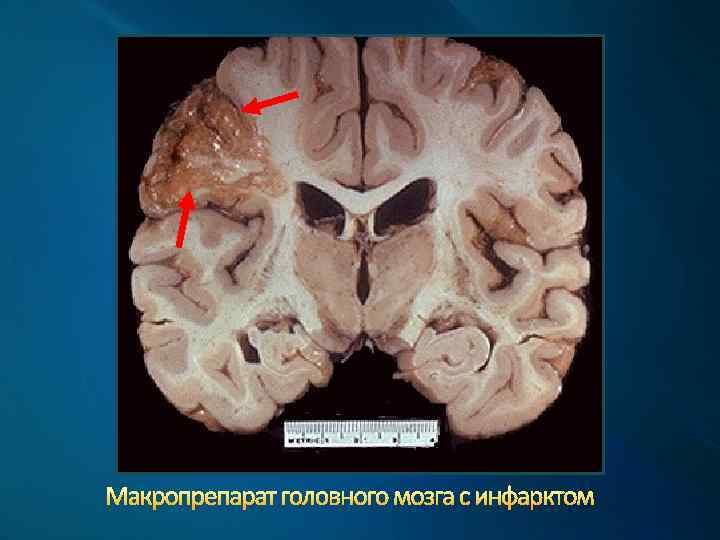

Макропрепарат головного мозга с инфарктом